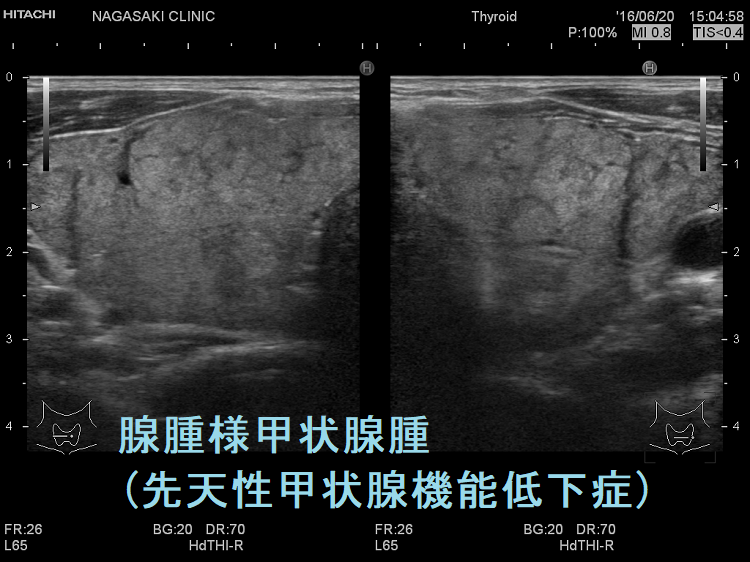

伊藤病院の報告では、

- 甲状腺腫を有する先天性甲状腺機能低下症患者の71%に、10mm以上の甲状腺結節が認められる

- 甲状腺腫あるいは甲状腺結節を有する先天性甲状腺機能低下症患者は、全例が遺伝性甲状腺ホルモン合成障害

とされます[ Thyroid. 2023 May;33(5):556-565.]。

遺伝性甲状腺ホルモン合成障害で、サイログロブリン異常症(サイログロブリン遺伝子異常症)以外は、血中サイログロブリンが上昇するにも関わらず、甲状腺自体の破壊性変化に乏しく、マシュマロ様の軟らかい腺腫様甲状腺腫の形態を取る事があります。

ケース⑤

ケース⑥

他の甲状腺ホルモン合成障害と同じく、マシュマロ様の軟らかい腺腫様甲状腺腫の形態を取ります。しかし、サイログロブリン遺伝子異常症と異なり、癌の発生は稀です。

遺伝性甲状腺ホルモン合成障害の超音波(エコー)画像は色々なパターンがあります。

- 常染色体優性遺伝型;腺腫様甲状腺腫の形態になります。